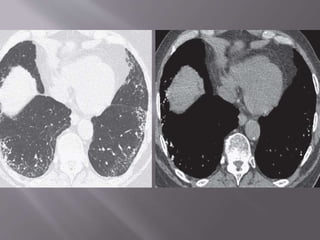

 The histologic findings of acute exacerbation of IPF

HRCT manifestations consist of extensive bilateral

ground-glass opacities and/or consolidation

superimposed on reticulation and honeycombing.

Patients with acute exacerbation have a poor

prognosis with mortality exceeding 60%.